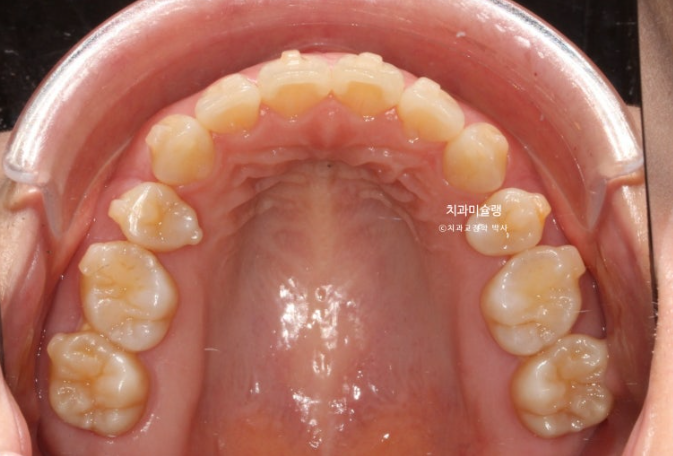

26.01

이제 전후 비교 보겠습니다.

총 치료기간은 3년 2개월, 재제작은 3회 했습니다.

어금니 교합은 뜨는 곳 없이 좋습니다.

중심선은 정확히 맞아졌습니다.

발치공간도 거의 없어졌습니다.

아래 앞니는 계획대로 뒤로 1mm도 뒤로 들어감 없이 잘 유지가 되었고 위 앞니는 치조골이 허용하는 범위 내에서 아래앞니와 만나기 위해 최대한 뒤로 들어갔습니다.